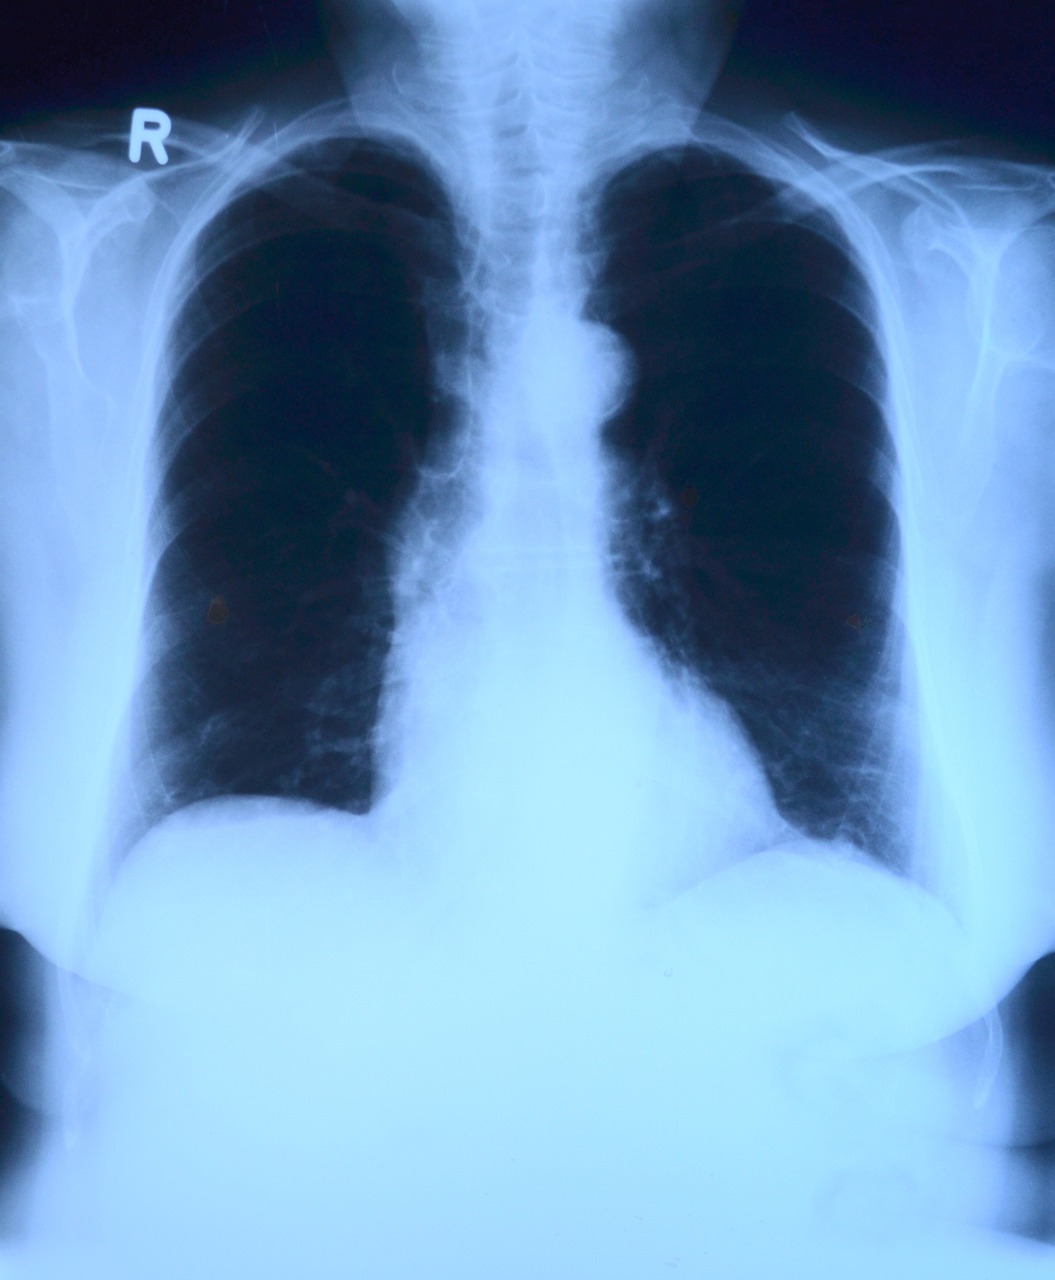

I also needed to submit a complete laboratory test results and I am not sure if it would include a chest x-ray, 2D echo, or at least an ECG test. I had both gotten tested for the said tests as a requirement to get a clearance about my AV fistula's surgery and I did passed them because otherwise I will not get that surgery. That is why I was very happy to learn that I do not have a heart condition which means that I might live longer than I am expecting although my liver condition will have the last laugh over my existence.